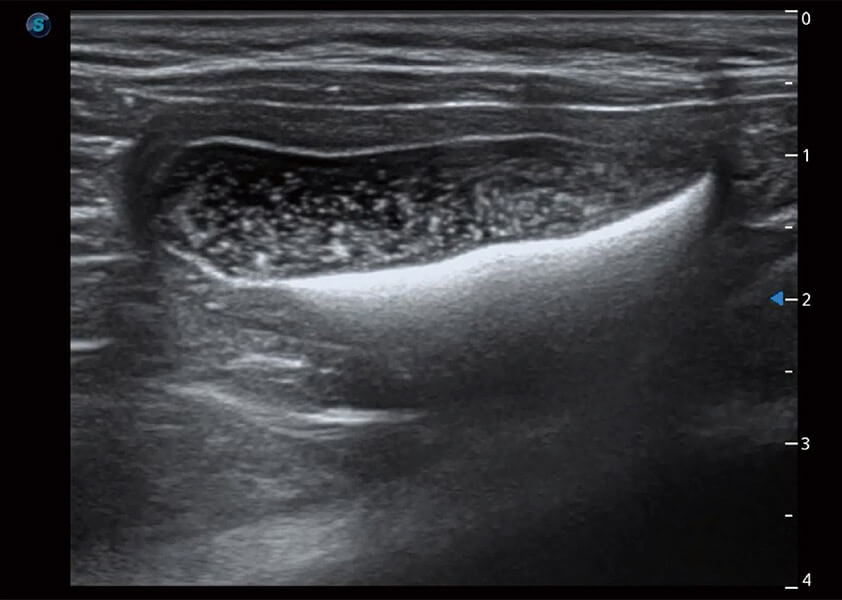

ProPet 60 作为一款高端台式动物超声设备,为动物医生的日常诊断提供了一系列贴合动物临床需求、解决临床实际问题的高级成像功能。凭借全系列高清探头,满足医生对腹部、心脏、生殖、浅表、肌骨等成像的所有需求,切实帮助您提升检查效率,提高诊断信心。

动物是人类最亲密的朋友和最值得信赖的伙伴。狗万官方网站也一直致力于探索动物专用的超声影像解决方案。 全新推出的ProPet系列,是狗万官方网站在动物超声影像智能化、专业化、精准化的一次跨越式革新。动物不能用言语来表述自己的不适,通过超声影像,ProPet系列搭建了动物医生与不同物种沟通的“桥梁”,为动物医生注入了“治愈之力”。